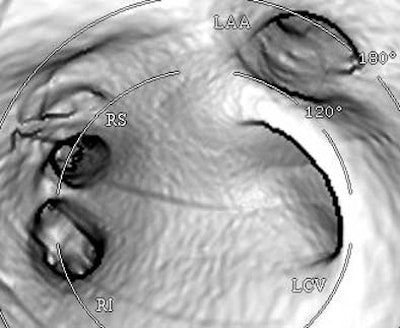

![]() |

| Endocardial (above) and epicardial (below) views from a patient with a long-trunk left common vein (LCV) and separate RS and RI veins. There are a total of three pulmonary veins. (LAA = orifice of the left atrial appendage.) Images courtesy of Dr. Joan Lacomis. |

Pulmonary vein anatomy varies widely, and right-side anatomy tends to be more complex than the left side, she said. At her institution, a third of patients have been found to have accessory veins, she said, usually on the right side (87%). Conjoined veins are less common (10%) and usually occurred on the left side (88%). About 70% of patients in the past five years have been reported to have the classic fourth pulmonary vein, and some form of variant PV anatomy is present in about 30%-40% of patients. Long-trunk common veins are easy to diagnose, short-trunk common veins more difficult, she said.